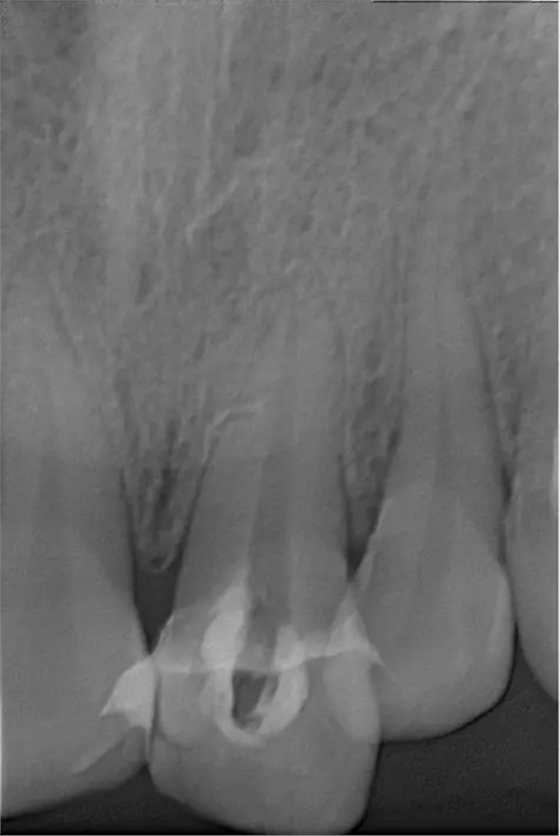

翻瓣去除側(cè)穿超出的牙膠尖

術(shù)后縫合